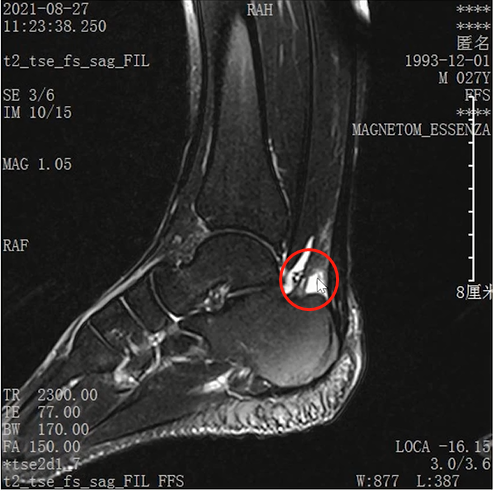

Lisfranc损伤在多发伤病人中常常容易漏诊,大约为 20-30%的漏诊率!